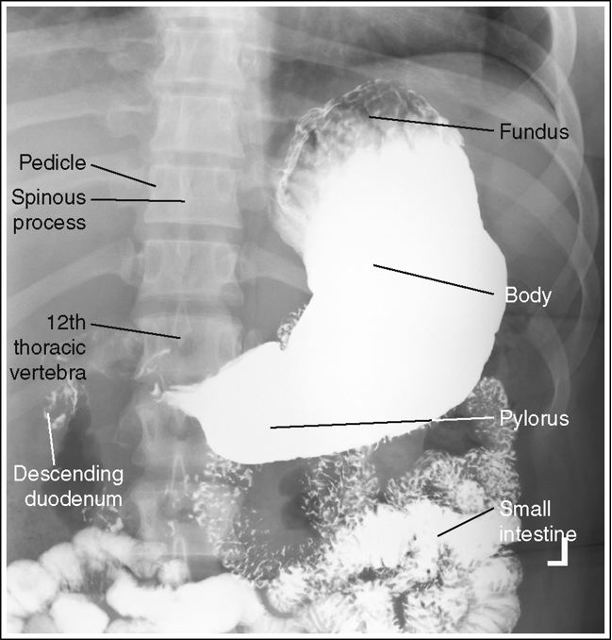

Lateral Stomach and Duodenum (CR and positioning)

Recumbent Right Lateral - Visualized the right retro-gastric space, duodenal loop and the duodenaljejunal junction

Upright left lateral - Visualized the left retro-gastric space

11×14 IR

CR - At the level 1-2 inches above the lower rib margin (L1-L2) Center between the midcoronal plane and the anterior surface of the abdomen

Mark right side down - anterior

Suspend respiration at the end of expiration

Shield gonads

Lateral stomach with proper positioning

Lateral stomach descending duodenum is partially superimposed over the duodenal bulb and vertebrae, and the posterior surfaces of the thoracic and lumbar vertebrae are not superimposed. Patient was not in a true lateral position